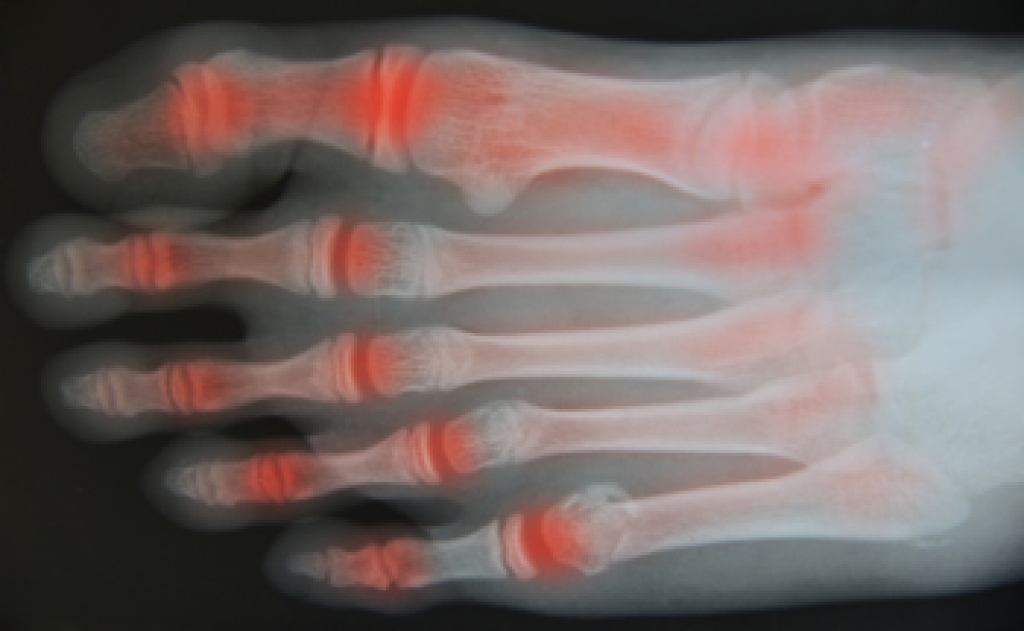

Diagnosis

Diagnosis of cuboid syndrome is often difficult, and it is often misdiagnosed. X-rays, MRIs and CT scans often fail to properly show the cuboid subluxation. Although there isn’t a specific test used to diagnose cuboid syndrome, your podiatrist will usually check if pain is felt while pressing firmly on the cuboid bone of your foot.